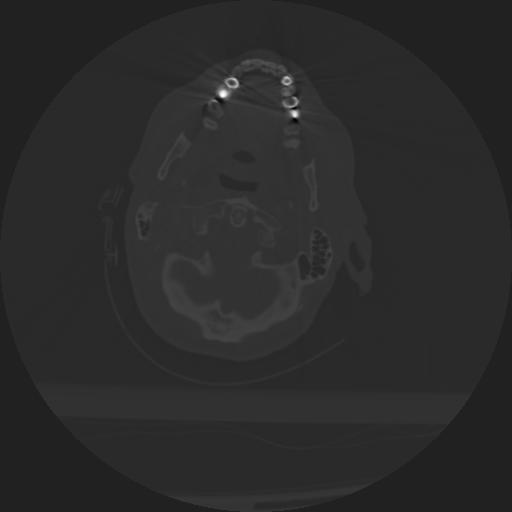

22 ANGIO,CE,Vol,0.5,ANGIO,,